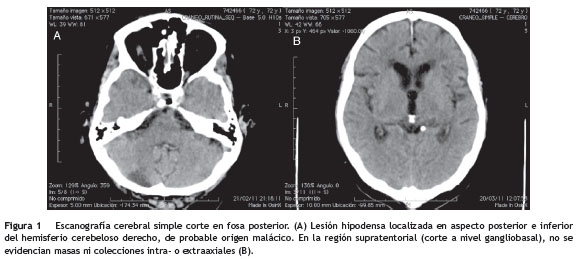

Se realizó punción lumbar de control al día 12 de tratamiento, con los hallazgos descritos en la tabla 1- B. Adenosina deaminasa (ADA) en 6,9 y ELISA para VIH, negativo. Permaneció hospitalizado por 37 días y dieron egreso. Tres días después presentó somnolencia, desorientación y alucinaciones visuales y consultó a nuestra institución. Al ingreso, somnoliento, desorientado y con lesiones subdérmicas en piel de consistencia blanda no adherida a planos profundos y dolorosas a la palpación, localizadas en extremidades. Se realizó escanografía cerebral simple que documenta leucomalacia en región cerebelosa derecha (fig. 1A), sin lesiones ni masas extraaxiales agudas (fig. 1B).